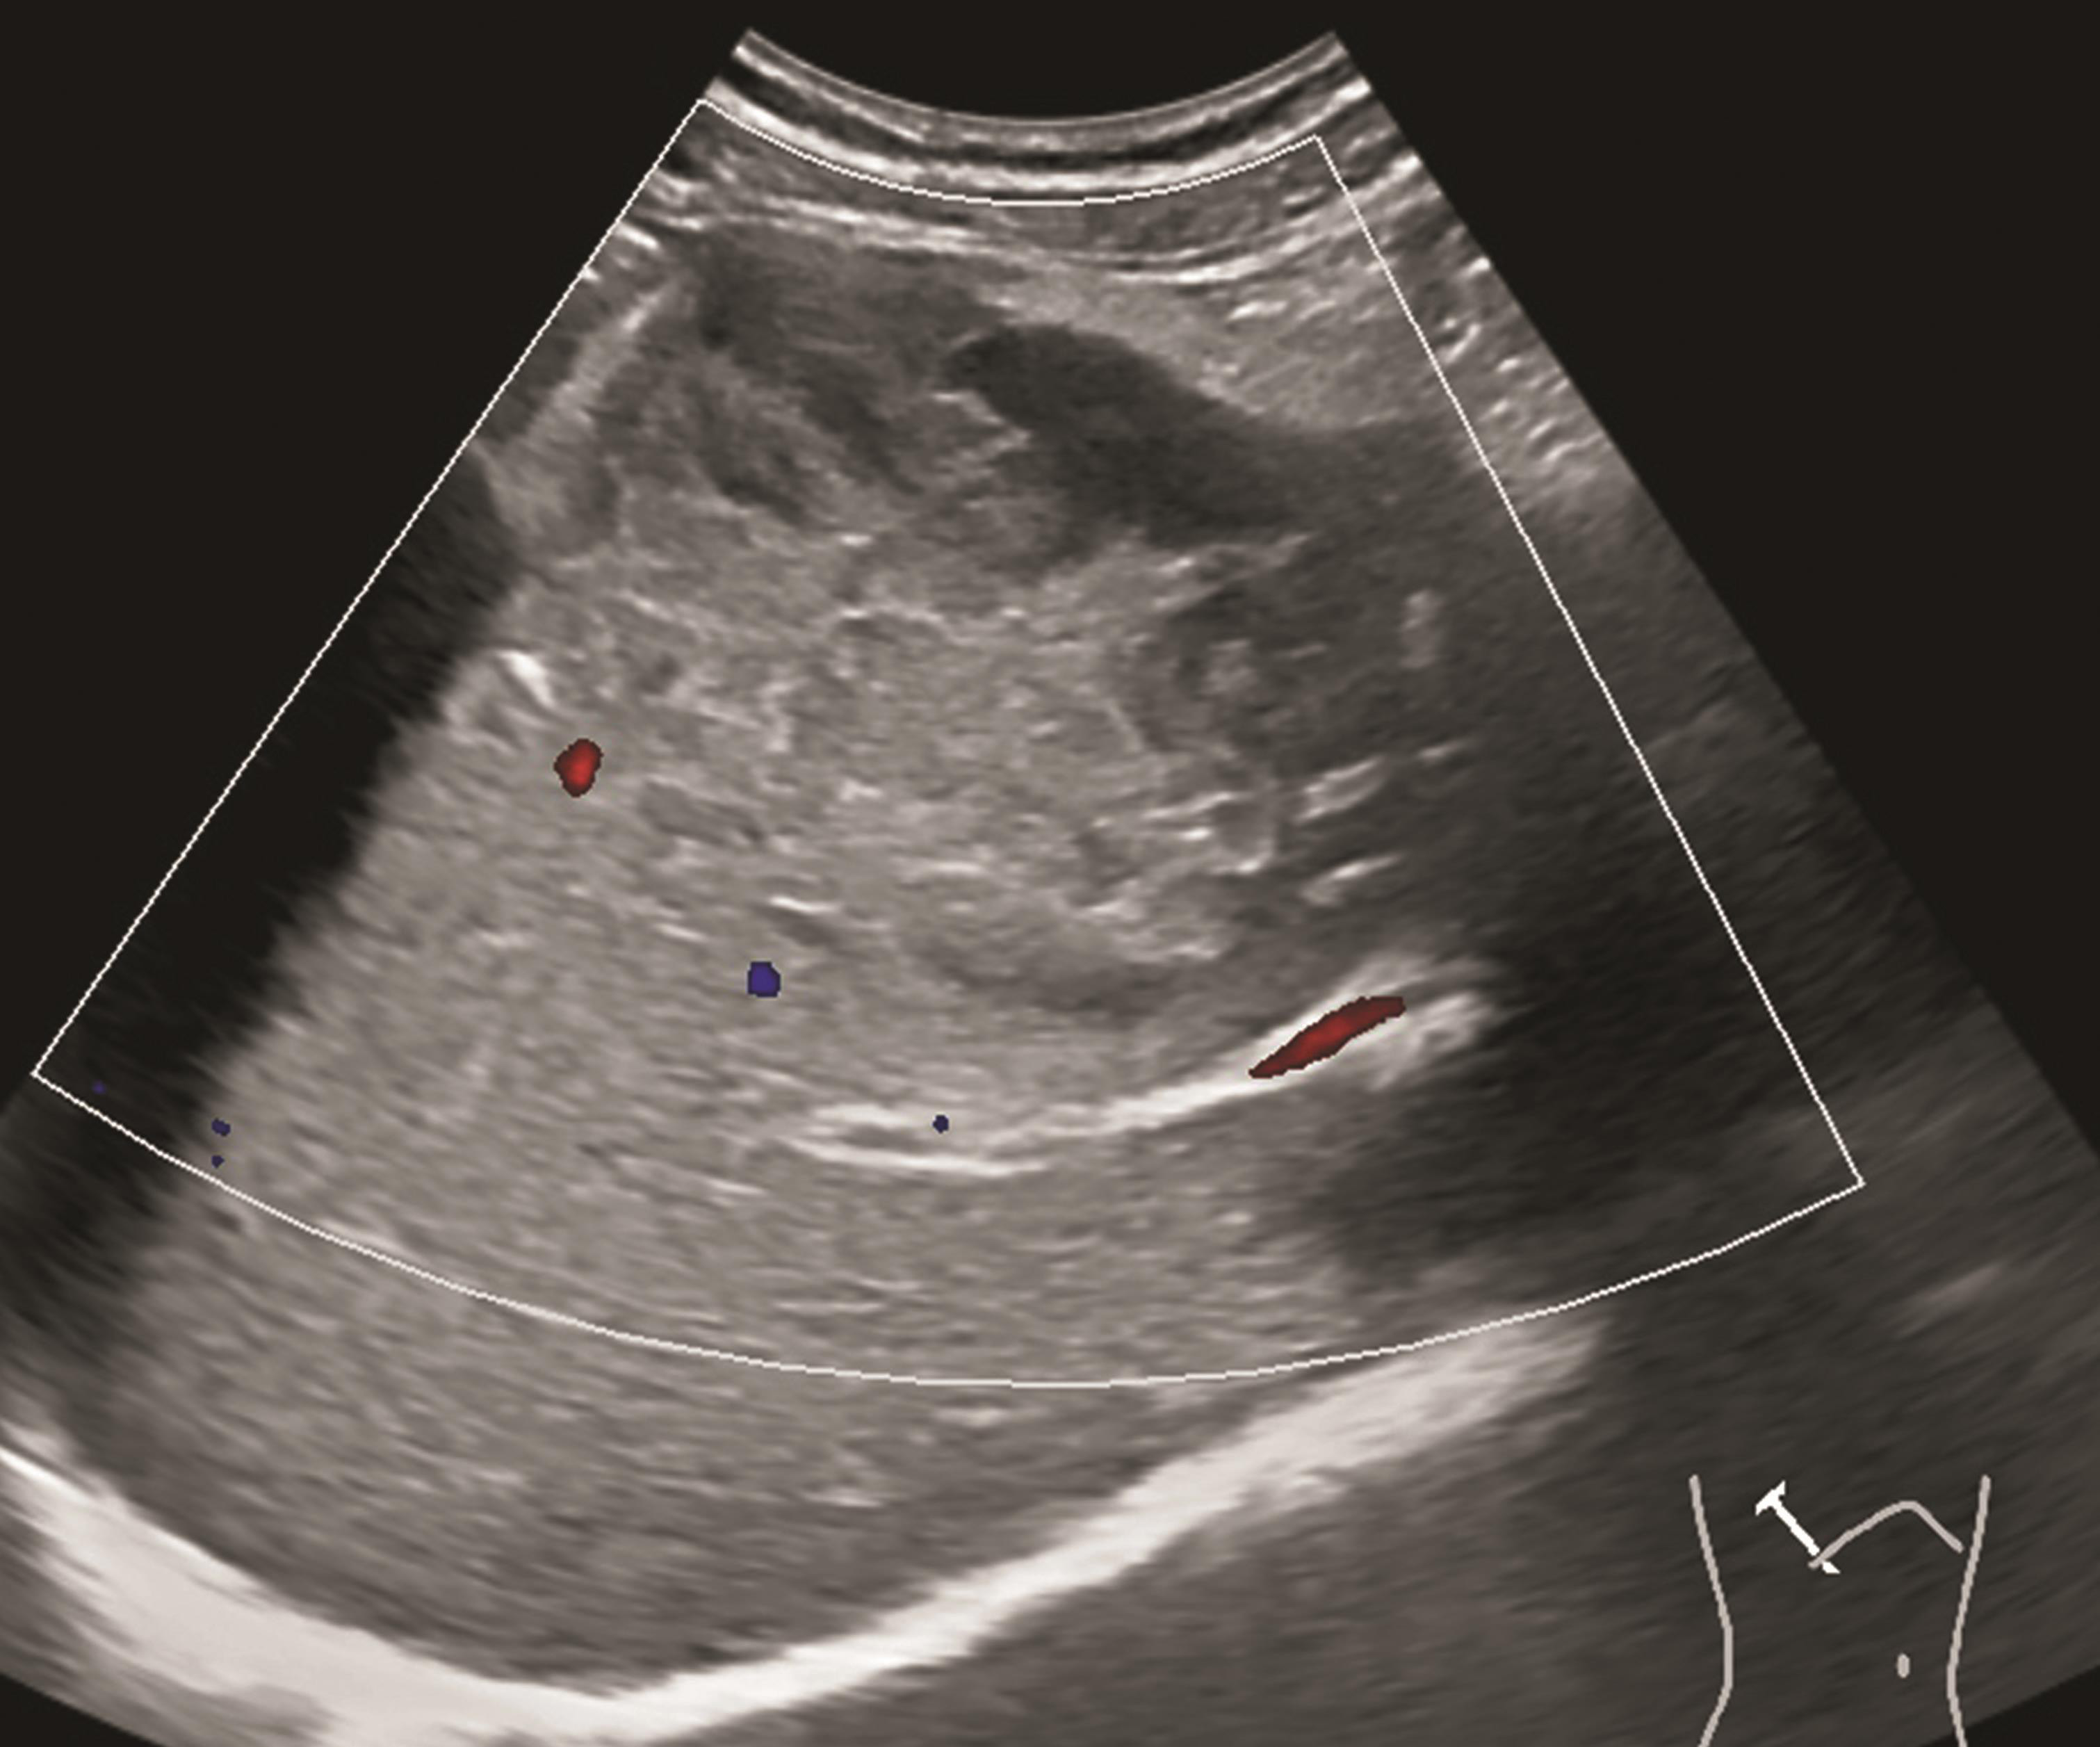

图1-7-2 肝细胞癌CDFI图像

CDFI显示癌结节内部及周边未见明显血流信号